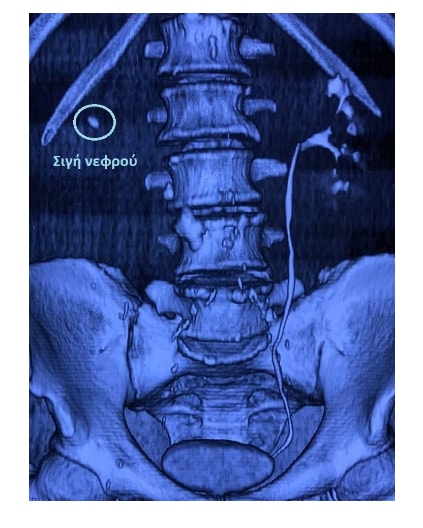

Η αντιμετώπιση της αποφρακτικής ουροπάθειας περιλαμβάνει την άμεση παροχέτευση των ούρων, ιδίως στην περίπτωση της επιπλοκής με λοίμωξη ή έκπτωσης της νεφρικής λειτουργίας.

Η παροχέτευση των ούρων μπορεί να γίνει, ανάλογα με το επίπεδο της απόφραξης, είτε με καθετηριασμό της ουροδόχου κύστης, του ουρητήρα ή και με νεφροστομία.

Αν τα δύο αυτά μέτρα παρθούν έγκαιρα, η έκπτωση της νεφρικής λειτουργίας είναι αναστρέψιμη. Σε δεύτερο χρόνο πραγματοποιείται αντιμετώπιση της υποκείμενης αιτίας.